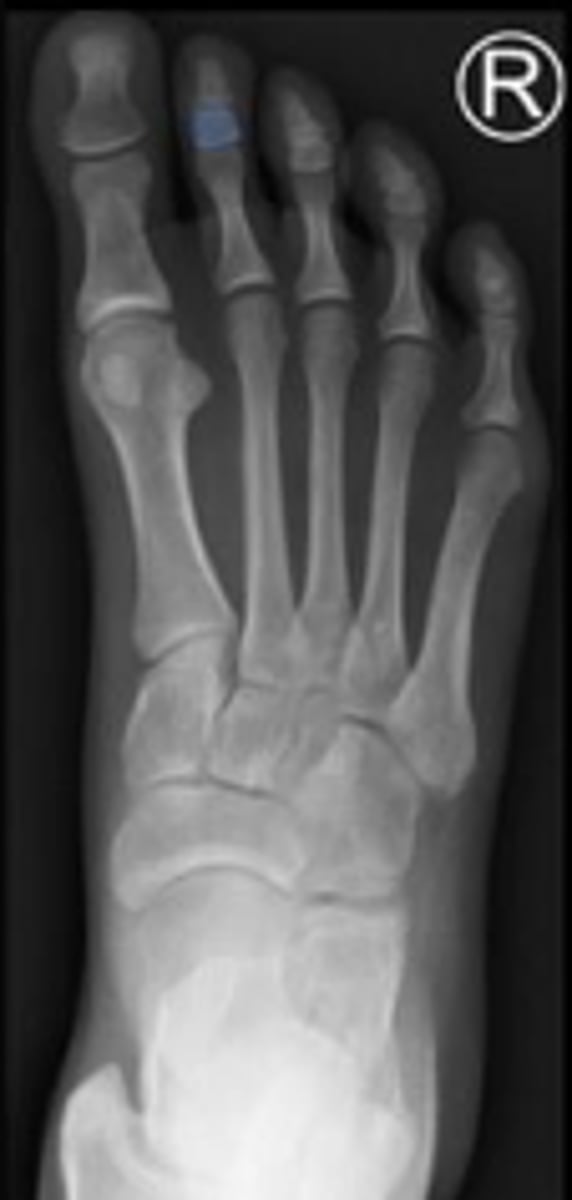

AP right foot

What is the name of the radiographic view?